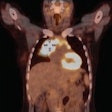

FDG-PET/CT can direct biopsies for pediatric cancer

March 8, 2017